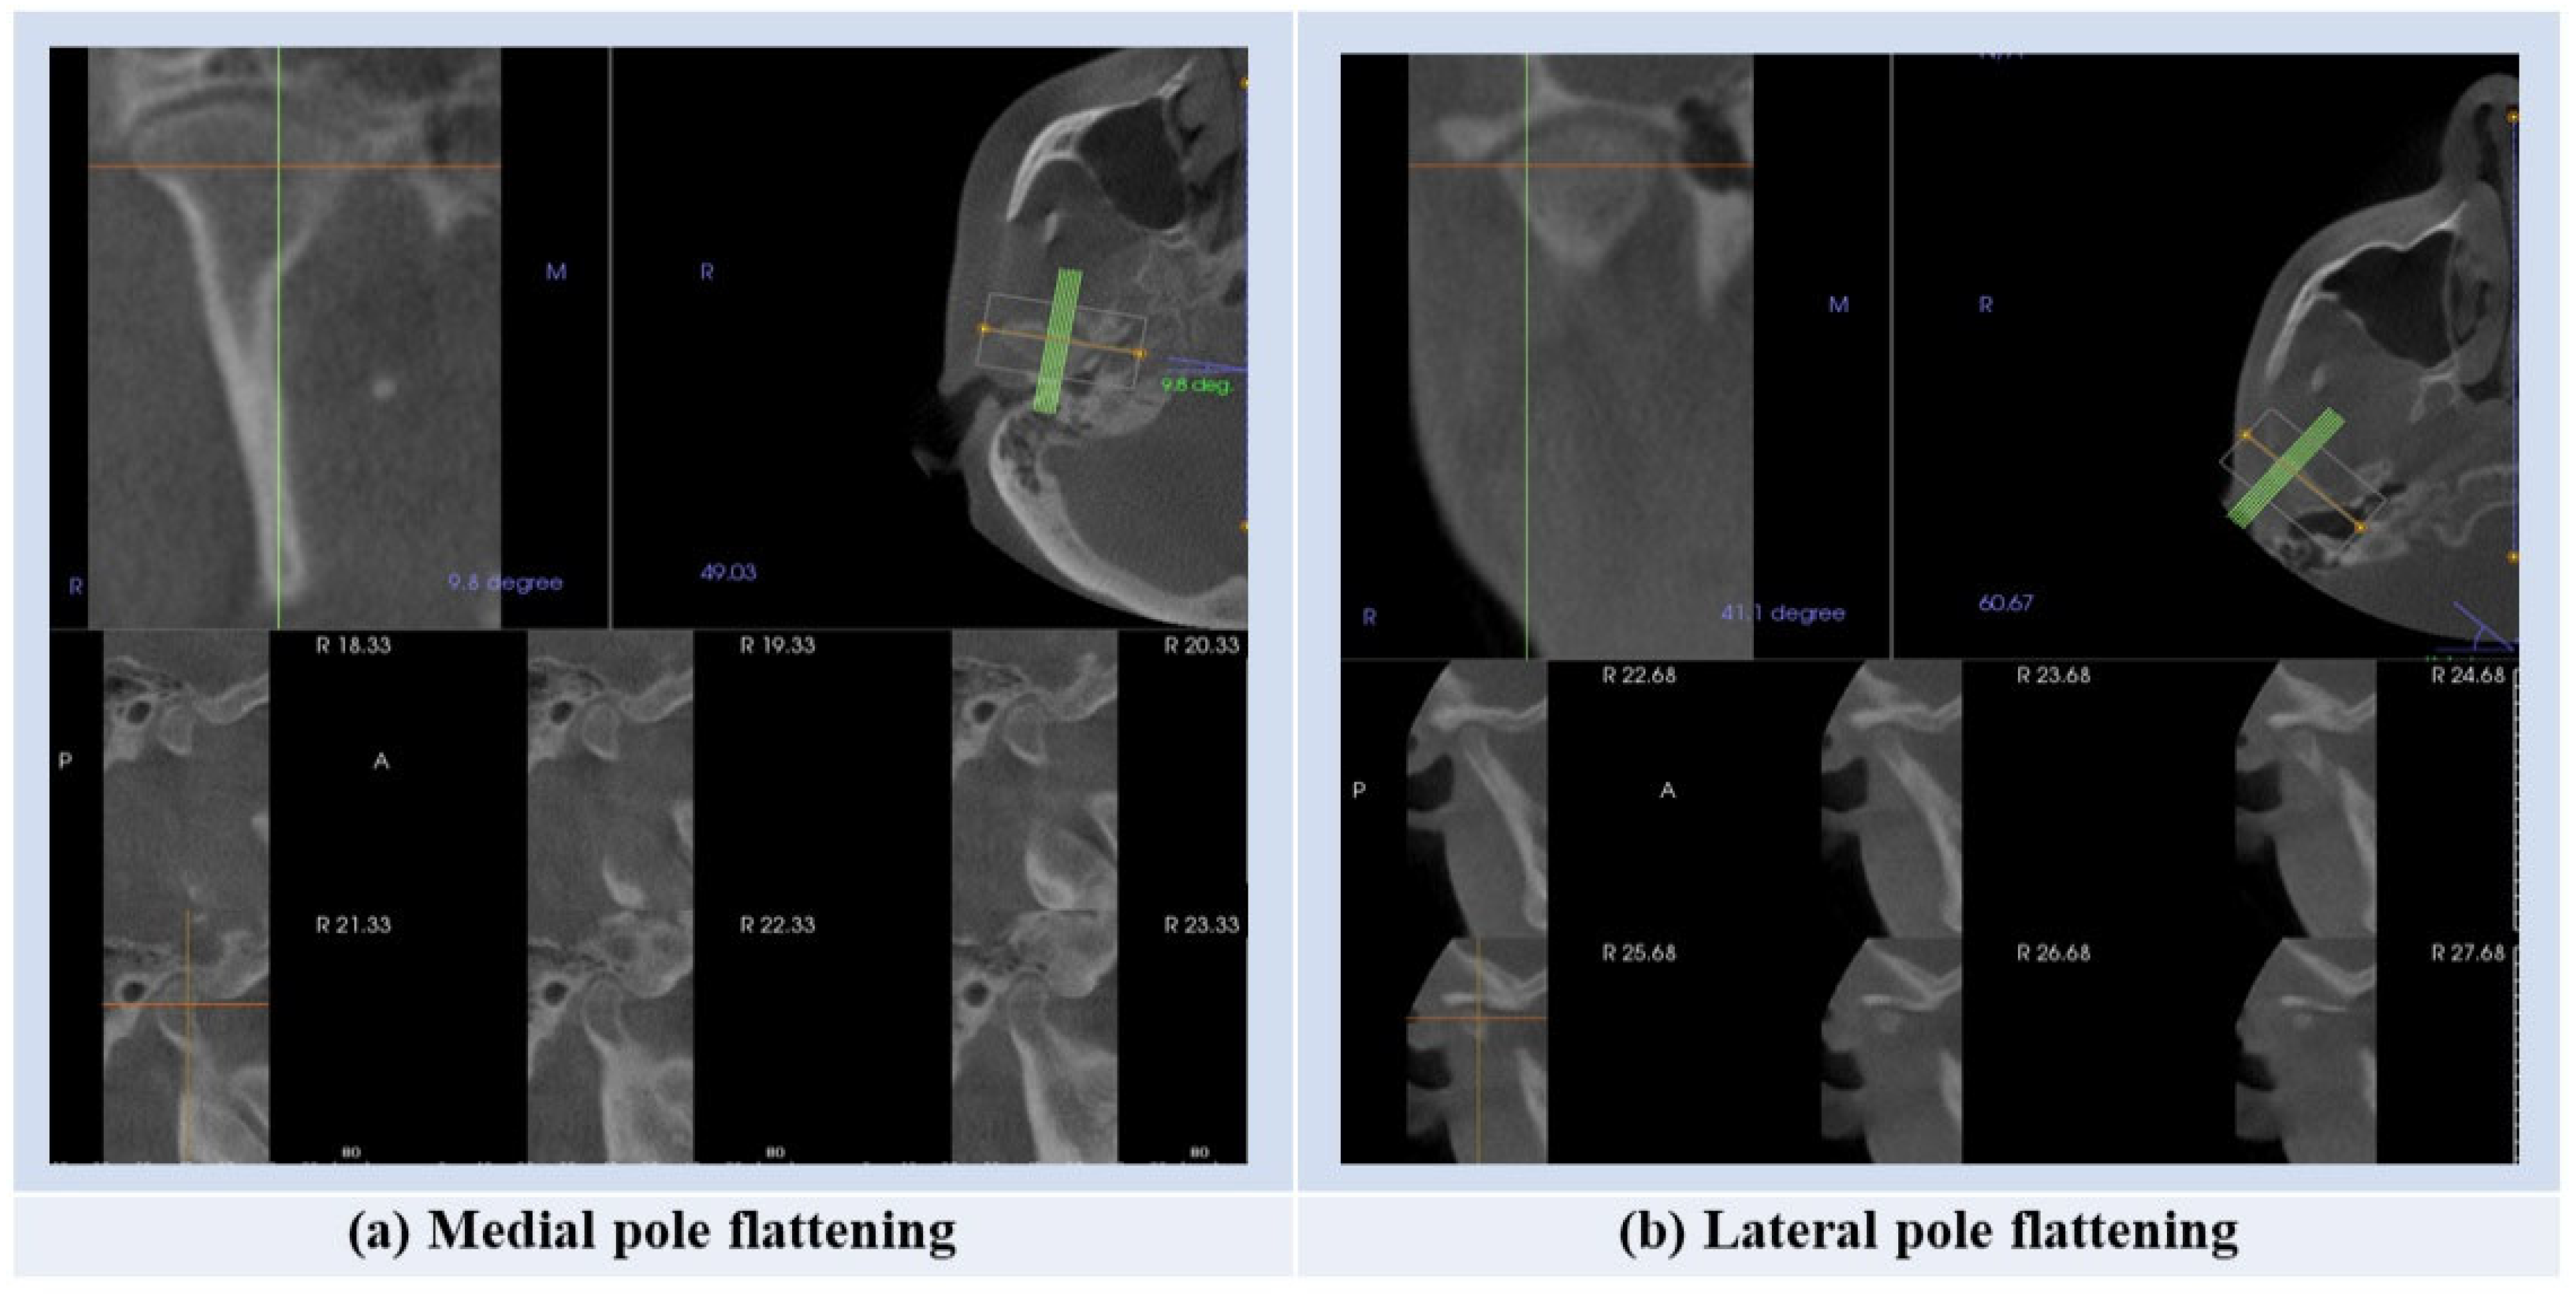

To analyze the scans, first, the scan was presented into the reconstruction program in the sagittal view keeping the horizontal reference line passing through the middle portion of the palate. Next, the standardized layout of frontal, axial, and 6 laterals was selected on the TMJ view. Later, adjustments were made to the TMJ view of the software where the area of the TMJ was placed in the view. While analyzing the data, the slice section was taken from the middle of the condyle on the axial view. Then, the condylar head shape was determined by looking at the slice view using the parameters of width = 0.8 mm, interval = 0.25 mm, and thickness = 0 mm [16]. The CBCT scan was then evaluated by viewing the condyle in the coronal plane and categorizing it into one of four shapes: flat, round, angled, or convex [16]. The flattening and degenerative changes were analyzed on the sagittal view by viewing the slices of the medial and lateral poles. Any changes in the condylar head except flattening were taken as degenerative changes, including subchondral sclerosis, subchondral cysts, erosions, and osteophytes, even if one radiographic feature was present.

The flattening of the medial pole was present in the left condyle in 33.3% of cases, while for the right condyle, flattening of the medial pole was present in 39.3% of cases (Table 1, Figure 2).

Figure 2.

The steps for assessment of the presence of the condylar flattening.

The flattening of the medial and lateral poles appeared in 33.3% and 47.9% of the left condyle, respectively. In contrast, for the right condyle, the flattening of the medial and lateral poles appeared in 39.2% and 46.5%, respectively (Table 3). Degenerative changes for both the left and right condyles were present in 32.6% and 32.3%, respectively (Table 3).